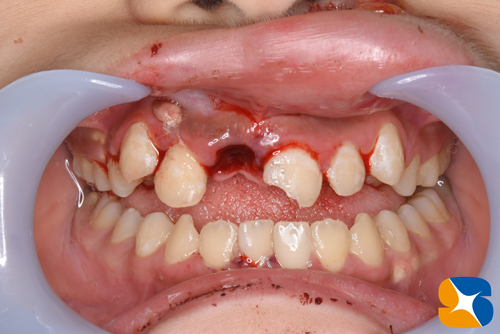

早速、矯正で使用する材料を用いて(保険の500円のみ、特殊な材料代は無料)前歯を元の場所に戻し、スーパーボンドで固定しました。

お子さんには頑張ってもらい、膿の袋を取り出す手術を行うことにしました。

採血した血液を用いてCGF(RPR法)を行なって骨の欠落したところに埋めました。(保険ではPRP法の設定はないため無料)

更に人工の骨も充填(無料)して完了しました。